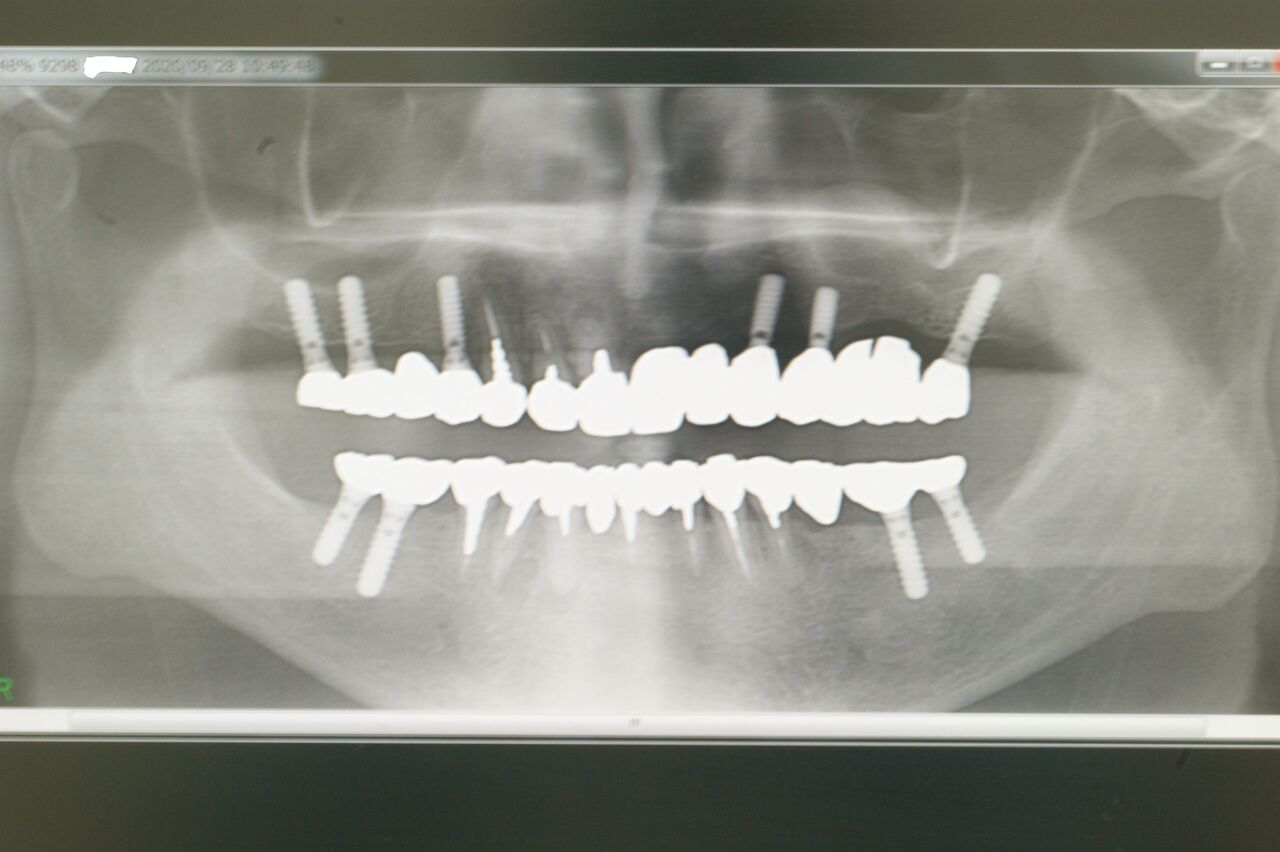

上のX線はある患者さんの初診時で、右上の脱離ブリッジを主訴として来院され、下顎には既に部分床義歯が装着されていました。

上顎は残存歯3本、インプラントでなく部分義歯を装着すれば、将来総義歯に移行するであろうことは火を見るよりも明らかです。インプラントによって、咬合の確立ができただけでなく、残存歯の寿命を延ばしめたところに、最大の意義があるのではないかと考えています。(大)